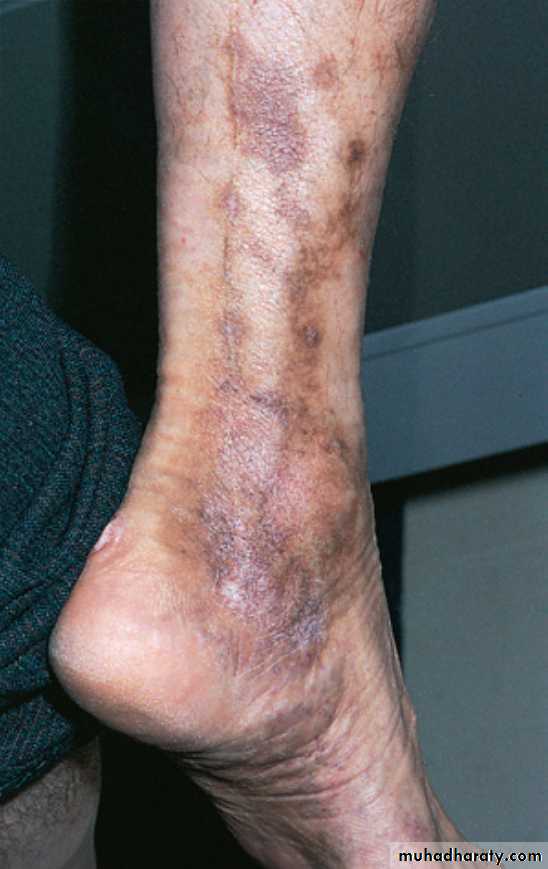

Thrombophlebitis (vasculitis) in Behçet’s disease. Inflammation and pigmentation highlight the sites of veins and their valves.